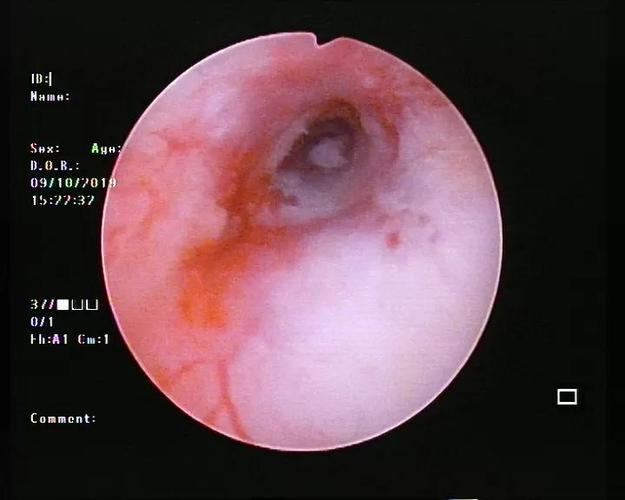

宫腔镜正常子宫图片

宫腔镜正常子宫图片,宫腔镜疼吗

正常的宫腔镜照片

宫腔镜下子宫内膜图片

宫腔镜子宫内膜炎图片

宫腔镜的正常结果图片